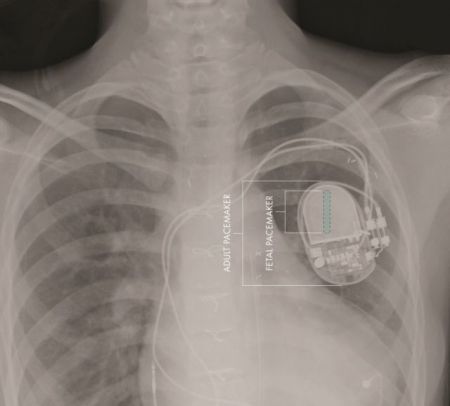

Ένας πειραματικός βηματοδότης που αναπτύχθηκε σε αμερικανικό νοσοκομείο είναι αρκετά μικρός ώστε να εμφυτευθεί στο αναπτυσσόμενο έμβρυο. Μέχρι σήμερα, οι μόνοι βηματοδότες που μπορούσαν να χρησιμοποιηθούν σε τέτοιες περιπτώσεις ήταν οι σχετικά ογκώδεις βηματοδότες για ενήλικες, οι οποίοι όμως δεν χωρούν στο σώμα του αναπτυσσόμενου εμβρύου.